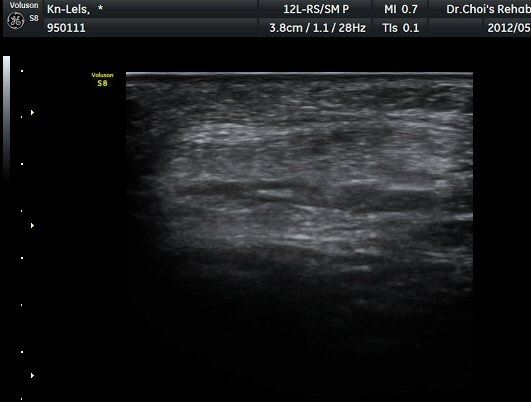

»çµÎ±Ù ÈûÁÙ Á¾´Ü¸é°Ë»ç¿¡¼­ ÈûÁÙÀÇ ºñÈİ¡ °üÂûµÈ´Ù9±×¸² 1, 2).